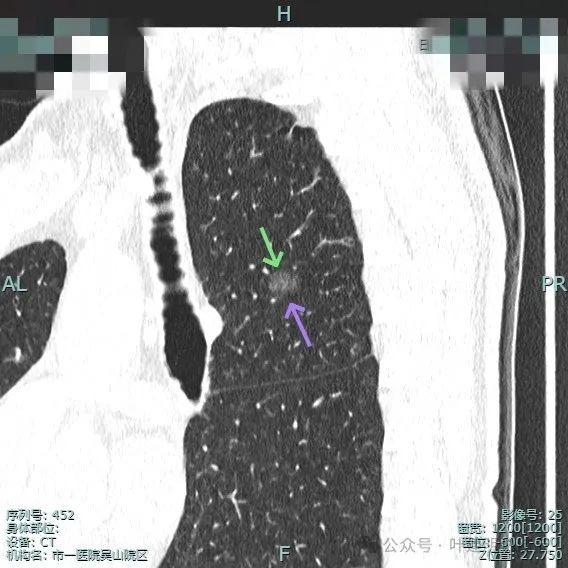

图片

主病灶术前定位,医用胶就在病灶边上(上图绿色的是定位医用胶,红色箭头指的是病灶6)。

次病灶术前定位,上图均是定位胶,结节太小,在其附近层面。